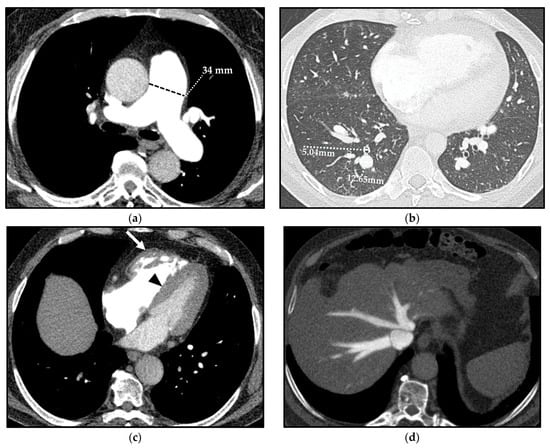

In patients with PH, the increase in PAP results in structural and hemodynamic changes that cause indirect vascular and cardiac CT signs, which should be recognized by radiologists (Figure 4).

Figure 4.

Computed tomography (CT) indirect signs of pulmonary hypertension (PH). Vascular CT signs: main pulmonary artery (MPA) dilation (34 mm) (a) and increased segmental artery-to-bronchus ratio (>1) (b). Cardiac CT signs: right ventricle (RV) hypertrophy, with free wall thickness > 4 mm and trabecular hypertrophy (arrow), and flattening of the ventricular septum (arrowhead) (c). Extensive reflux of contrast medium into the inferior vena cava and hepatic veins (d).

The vascular CT signs of PH reflect the underlying mural architecture of the vessels [16,17]. The multiple parallel elastic laminae that compose the wall of central pulmonary arteries (PAs) allow the caliber adaptation of main, lobar, and proximal segmental arteries to vascular bed resistance. On the other hand, a prevalent muscular component characterizes the distal segmental and subsegmental arteries, which are highly responsive to circulating factors and local stresses and are the most involved vessels in PH. Hypoxic vasoconstriction, vascular remodeling, and proliferative vaso-occlusive lesions usually occur at this distal level [16,17]. This is the reason why the earliest appreciable CT sign related to PH is the dilation of the proximal PAs and the sudden caliber decrease in peripheral ones [18].

A mean diameter of the main PA (MPA)—also known as the pulmonary trunk—(measured at its largest point within 3 cm of its bifurcation) ≥29 mm is predictive of PH with a sensitivity, specificity, and positive predictive value (PPV) of 87%, 89%, and 97%, respectively [19]; specificity increases up to 100% when the dilation of the MPA is matched with a segmental artery-to-bronchus ratio > 1 in 3 out of 5 pulmonary lobes on axial CT scans [19,20].

Moreover, the ratio between the diameter of the MPA and the diameter of the ascending aorta > 1 has been shown to have a sensitivity, a specificity, and a PPV of 70%, 92%, and 96%, respectively, for predicting PH in patients under 50 years of age [21]. Nonetheless, the negative predictive value (NPV) of this ratio is only 52%; thus, the absence of this parameter does not rule out PH [21].

Cardiac CT signs of PH depend on the exceeding adaptative mechanisms and subsequent failure of the RV.

Prolonged and severe PH ultimately impacts on the RV, and this is manifested as hypertrophy followed by dilation of the ventricular cavity and straightening of the interventricular septum, causing an abnormal septal movement that finally injures the left ventricle (LV) function [25]. On CT, an RV free wall thickness > 4 mm is used to define “hypertrophy” [26]. A CT sign of RV dilation, on axial images, is characterized by an RV diameter greater than that of LV up to LV compression in severe cases [27]. Straightening or bowing of the interventricular septum yields a sensitivity and specificity of 86% and 91%, respectively, for PH identification, usually evident when the RV pressure is >30 mmHg [28].

Reflux of contrast into the inferior vena cava and hepatic veins on first-pass contrast-enhanced CT (e.g., CTPA) is a specific and indirect sign of right heart dysfunction [29].